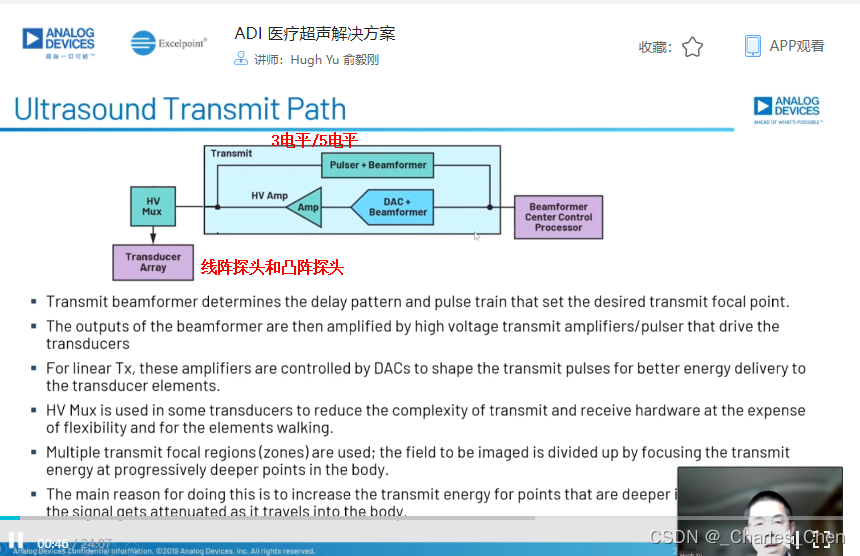

数字发射波束成形器用于产生所要求的数字发射信号,以正确的时间和相位生成聚焦发射信号。高性能超声系统可通过任意波形发生器产生复杂的发射波形,从而优化图像质量。这些情况下,发射波束成形器以大约40MHz速率生成8位至10位数字字符,并以此产生所要求的发射波形。数/模转换器(DAC)将数字波形转换成模拟信号,通过线性高压放大器进行放大,用于驱动传感器单元。由于这种发射技术占用较大体积,而且价格昂贵、需要消耗较高能量,所以,这种架构只限于昂贵的非便携设备。多数超声系统并不使用这种发射波束成形技术,而是采用多级高压脉冲发生器产生需要发射的信号。在这种替代方案中,利用高集成度、高压脉冲发生器快速切换传感器单元至适当的可编程高压电源,产生发射波形。为了产生一个简单的两极发射波形,脉冲发生器需要交替地将传感器单元切换到由数字波束成形器控制的正、负发射电压。更复杂的设计可以让传感器单元切换至多路电源和地,从而产生更复杂、性能更好的多重波形。